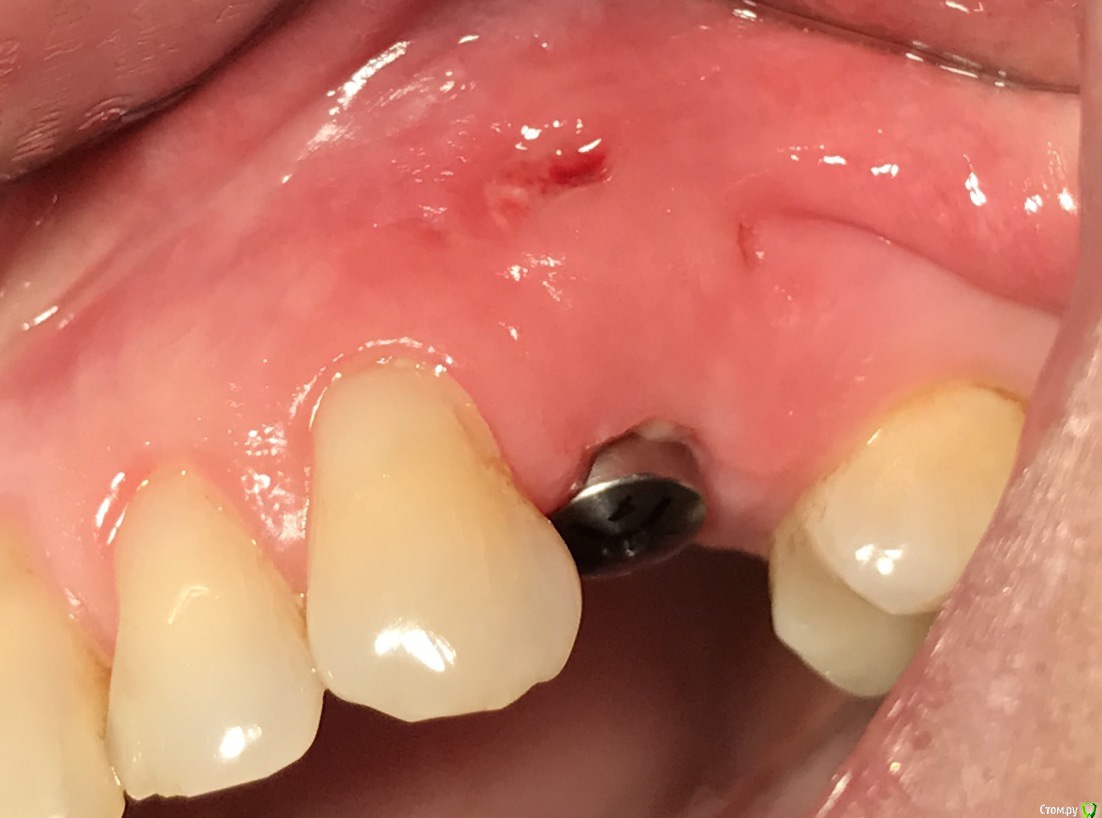

колесников Опубликовано 25 февраля, 2017 Поделиться Опубликовано 25 февраля, 2017 Здравствуйте коллеги! Представляю вашему вниманию этот клинический случай.В ноябре 2016 обратилась пациентка с жалобами на выпадение ортопедической конструкции в обл 24. Объективно: корни 24 не состоятельны. ,на десневом крае в проекции 24 свищевой ход с гнойным отделяемым.На КТ резорбция вестибулярной компактной пластинки и деструкция костной ткани в области щёчного корня.Приняв во внимание крайне негативное отношение пациентки к каким бы то ни было хирургическим вмешательствам и высоким эстетическим требованиям,было решено пойти на немедленную имплантацию .Снимки в день вмешательства,через 7,14 дней и 3мес.Имплант Astra tech profile 4.5х11мм. Сст с бугра вестибулярно. Вместо графта губки Коллапола (не вспомню причину,либо не было в наличии,либо отказ пациента). 15 Ссылка на комментарий

колесников Опубликовано 26 февраля, 2017 Автор Поделиться Опубликовано 26 февраля, 2017 Да,можно было ещё на 1мм притопить,и конечно графт вестибулярно оставить,но это стало понятно только сейчас. При постановке имплант был заглублен на 3 мм, посчитал что этого достаточно, но резорбция случилась больше планируемой. Первоначально планировалась нагрузка через 5 сут ,но ортопед позднее отказался от этой идеи. Думал заменить фдм на зебру,но пациентка пропала на 3 мес... Как получилось,так получилось. Торк был 35н/см,как обычно на астре. Ссылка на комментарий